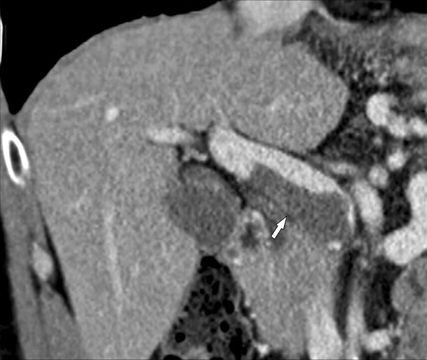

Zirrhose und „HCC mit Tumorthrombus“

Abb. 5: HCC mit Tumoreinbruch in die Pfortader: Die MDCT (koronale 3D-Rekonstruktion) zeigt den Kontrastmittel-aufnehmenden Tumor, der vom rechten Leberlappen in den rechten Pfortaderast vorwächst und diesen massiv aufweitet (Pfeile)

Die Bezeichnung „HCC mit Tumorthrombus“ ist irreführend und sollte nicht mehr verwendet werden, da es hierbei zu einem direkten Vorwachsen des HCC in die Pfortaderäste (u.U. bis in den Hauptstamm) kommt und nicht zur Bildung eines Thrombus. In der MDCT oder der MRT ist dafür typisch, dass man ein kontinuierliches Vorwachsen des HCC aus dem Parenchym in die Pfortaderäste erkennt. Der intravasale Tumoranteil weitet die Pfortader aus und zeigt ein Kontrastmittelenhancement wie der Tumor (Abb. 5), während ein blander Thrombus typischerweise keine Kontrastmittelaufnahme aufweist (Abb. 5). Der intravasale Tumoranteil muss daher auch wie ein Tumor behandelt werden und nicht wie eine Thrombose. Das American College of Radiology hat deshalb in seiner LI-RADS®-Guideline für die Beurteilung von hepatalen Knoten in der Zirrhose die KategorieLI-RADS TIV („tumor in vein“) geschaffen, um diese besondere Tumorentität von den HCC mit oder ohne PVT klar abzugrenzen.